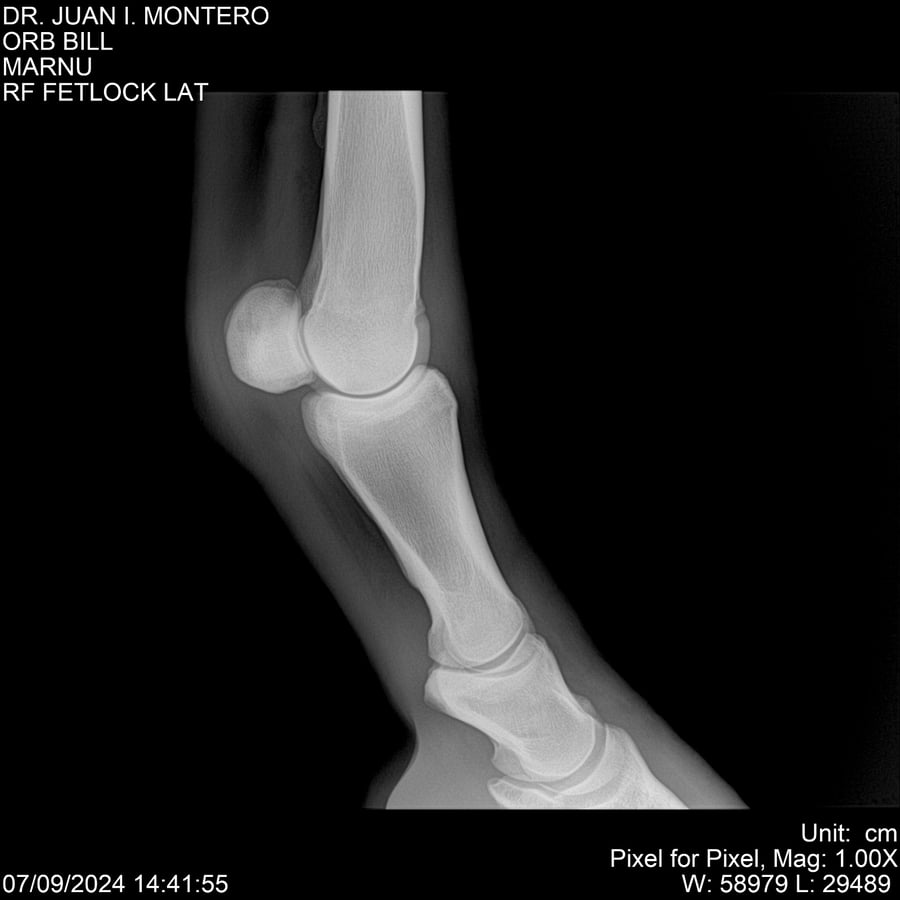

LOTE 7, ORB BILL 🔥 🔥 🔥 Lote Anterior Volver al remate Lote Siguiente Ficha Contacto Montevideo - Ficha del Lote Identificador: #282523 Categoría: Yeguarizos Montevideo - 83 Visualizaciones ClicData Contacto Empresa: Abelenda N. R., Walter Hugo Nombre*: Teléfono* : E-mail* : Mensaje Enviar Registrese gratis Este contenido Exclusivo está disponible sólo para usuarios registrados Ingresar